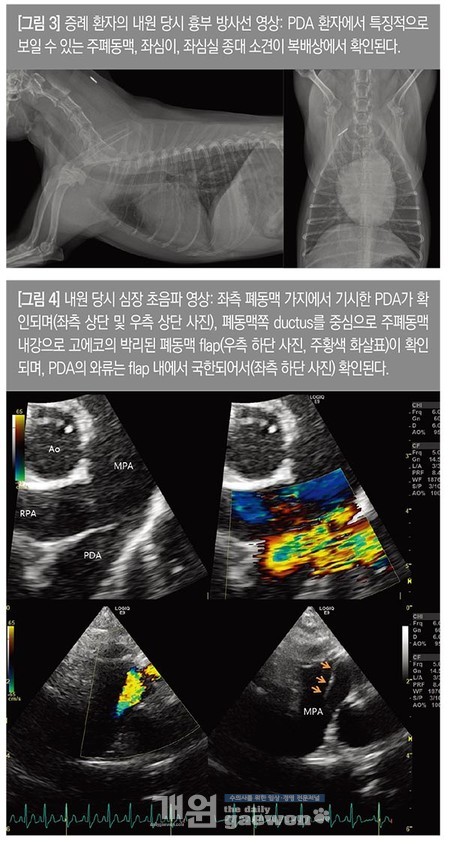

내원 당시 신체검사상, 심잡음(continuous murmur)이 청진되었고, 폐음은 양호하였다. 흉부 방사선 검사에서 주폐동맥, 좌심방, 좌심이 종대가 확인되었으며, 후엽 폐혈관의 울혈 소견이 동반되어 있었다. 심장 초음파 검사 상 좌측 폐동맥 가지 부근에서 continuous flow를 보이는 PDA가 확인되었으며, 수축기와 이완기 압력경사는 각각 104mmHg, 33.9mmHg로 측정되었다. B-mode에서 확인된 PDA의 형태는 type IIa 형태로 ductus의 직경은 2.2~2.4mm 가량으로 측정되었다.

이와 함께 폐동맥쪽 PDA ductus를 따라 고에코의 선형의 구조물이 확인되었으며, PDA를 통해서 폐동맥으로 유입되는 flow는 선형 구조물과 폐동맥벽을 따라 고립된(trap된) 양상으로 확인되어 폐동맥 박리가 병발한 것으로 진단하였다. 그 외 좌심방 확장 소견(LA:Ao 1.92), 이완기 좌심실 내강 확장 소견(LVIDDN 1.9)이 확인되었으며, 최초 의뢰병원 내원 당시에 확인되었던 폐수종 및 좌심방 압력상승을 지시하는 소견들은 모두 소실되었다[그림 3, 4].